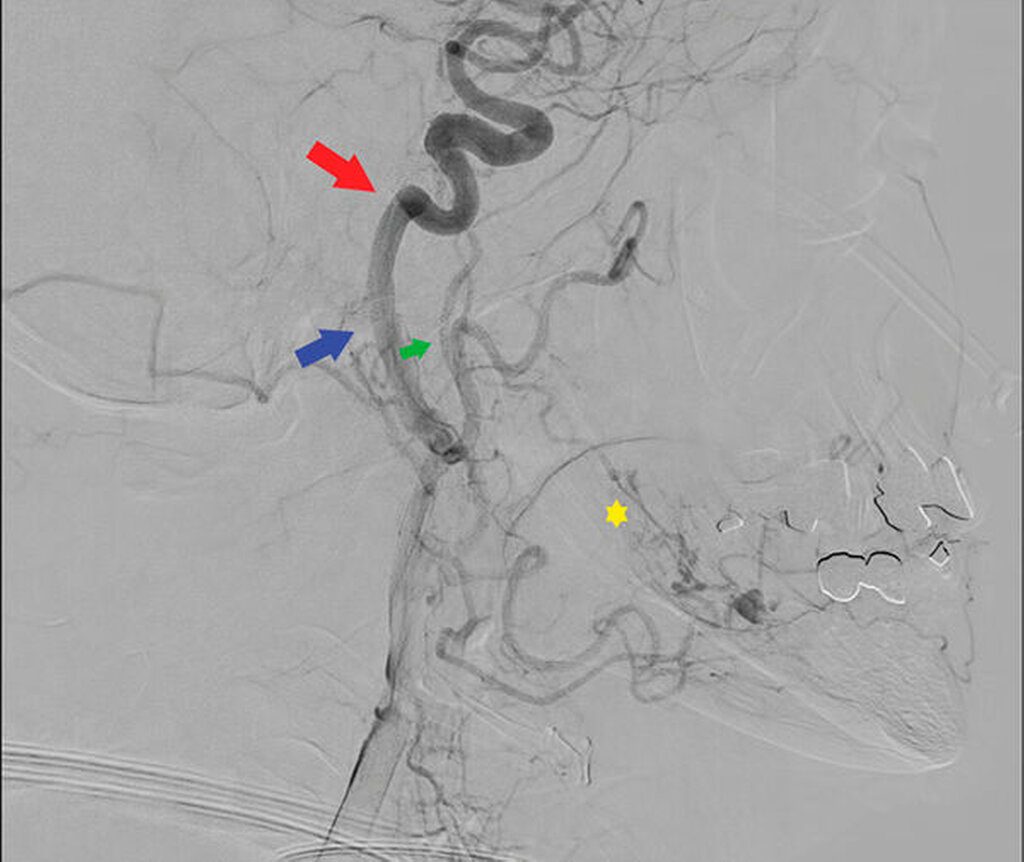

Nach der Diagnosestellung wird der Patientenfall im interdisziplinären Schädel-Basis-Board besprochen und die Patientin zur präoperativen Embolisation des Hämangioms und anschließenden operativen Resektion stationär aufgenommen. Im Rahmen einer superselektiven digitalen Subtraktionsangiografie wird das zuführende Gefäß, die Arteria alveolaris inferior, mittels Histoacryl vollständig verschlossen (Abbildung 4).